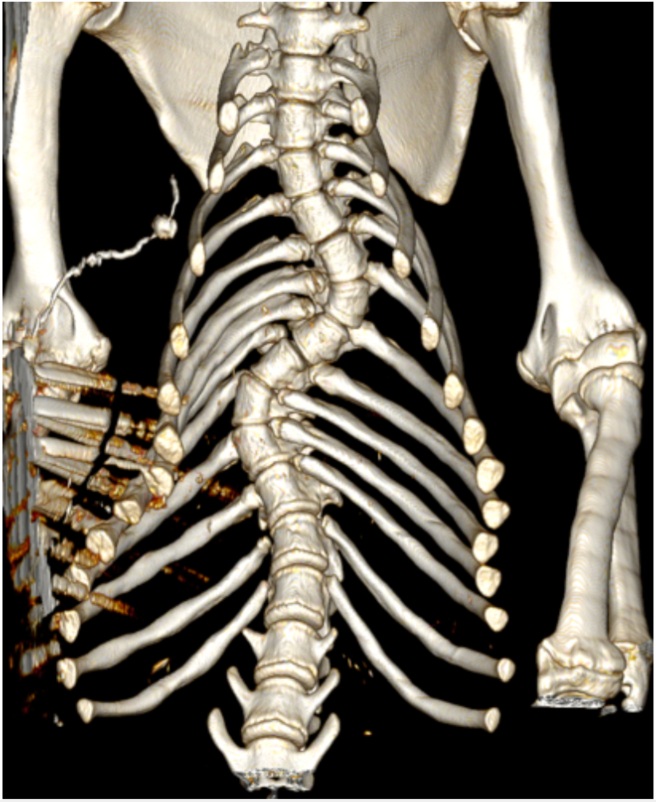

Uit de CT-scan werd duidelijk dat Tzigane een flinke afwijking aan zijn wervelkolom had, die mogelijk is aangeboren. Hierdoor is zijn borstkas misvormd en is er minder ruimte in de rechterkant van zijn borstholte. Hoewel Tzigane’s hart dus niet bijzonder groot bleek, was een er wel een deel van zijn longen aangetast. Dit komt waarschijnlijk door het gebrek aan ruimte in zijn borstkas.

Tzigane scan

De scan laat een duidelijke kromming van Tzigane's wervelkolom zien.